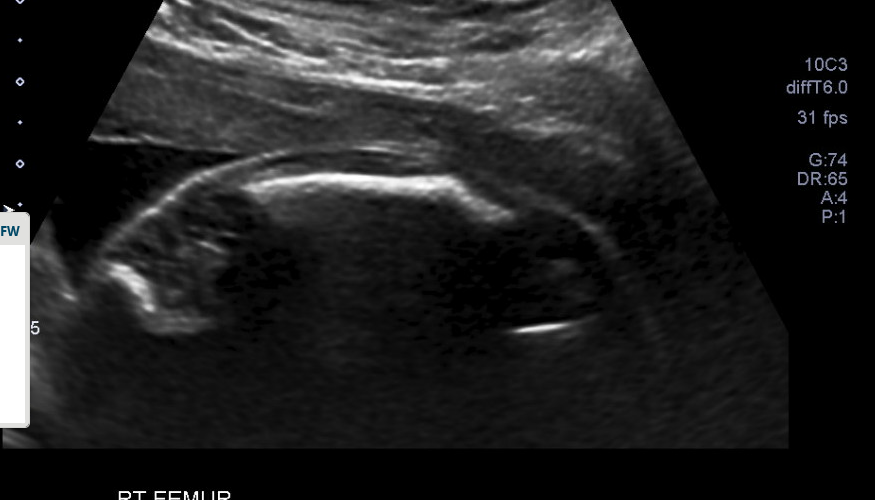

As Anna has Type 4 OI, she had in-utero findings that were monitored by the Maternal Fetal Medicine team. She had demineralization of bones, healing fractures in the femur, bowing of the femurs (but not humeri), and was measuring small for gestational age. It is important to note that she measured small because her long bones are bowed, underestimating their true length, and both her parents are under 5 feet, meaning her interval growth was appropriate but low against the population average.

At each serial ultrasound appointment, the sonographer evaluated existing fractures during and looked for new breaks, particularly in the long bones. It is, therefore, so important to really zoom up the images so that the area of focus takes up 80-90% of the screen, as this can be extremely subtle. The sonographer would also monitor ribs to make sure they were structurally sound and growing properly, as pulmonary hypoplasia is a serious complication.

Bowed long bones

Femur length ratio to biparietal diameter is lower than normal, ranging from 0.3 to 0.36 instead of the usual 0.44 (Murrin et al., 2022)

Femur length to foot length is between 0.76 and 0.94, compared to the normal range of 0.94 to 1.1 (Murrin et al., 2022)

Femur length to abdominal circumference ratio less than 0.16 is lethal in 92-96% of cases, with worse fetal outcomes in the combined presence of polyhydramnios (Murrin et al., 2022)

Chest circumference to abdominal circumference ratio of less than 0.6 is lethal in 86% of cases (Murrin et al., 2022)